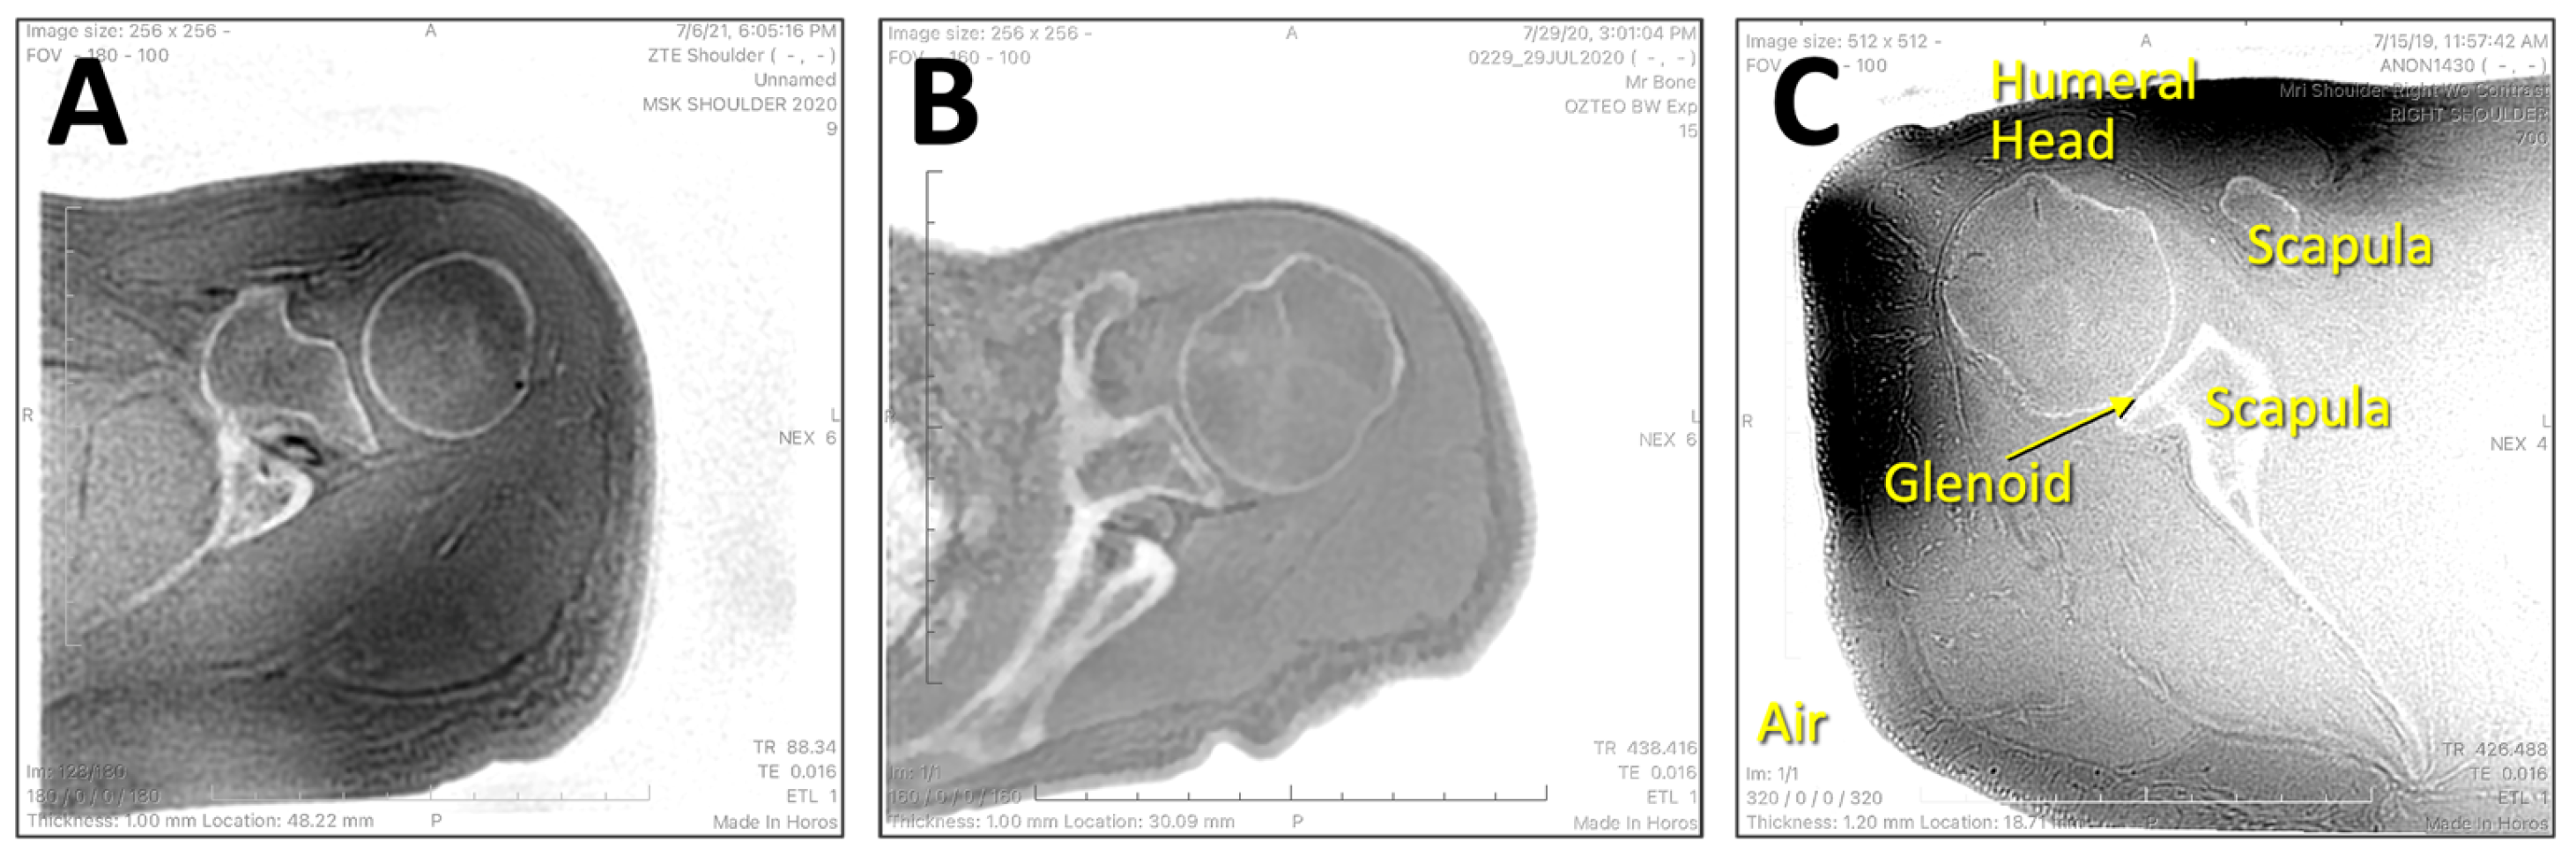

Figure 2.

Inverted axial ZTE shoulder images used in this study were acquired with moderately varying scan parameters. (A) was acquired with TR = 88 ms, TE = 0.016 ms, FOV = 180 mm, matrix = 256 × 256, and 1 mm slice thickness. (B) was acquired with TR = 458 ms, TE = 0.016 ms, FOV = 160 mm, matrix = 256 × 256, and 1 mm slice thickness. (C) was similar to (B) but acquired with FOV = 180 mm, matrix = 512 × 512, and 1.2 mm slice thickness. While varying in image contrast, all images shared a similar feature of depicting the bones of the shoulder with high signal intensity.

Training Data: For deep learning (DL) training data, we obtained a de-identified MRI shoulder dataset through an existing study where 7935 images from n = 31 normal asymptomatic unilateral (left or right) shoulders, acquired on General Electric 3-Telsa scanners, were available. The images were acquired in the axial plane using the ZTE sequence with mixed scan parameters: Time-to-Repetition (TR) = 100 to 600 ms, Time-to-Echo (TE) = 0.016 to 0.028 ms, field of view (FOV) = 160 to 240 mm, image matrix = 256 × 256 to 512 × 512, slice thickness = 0.7 to 1.2 mm, number of slices = 90 to 200. Despite some variations in the scan parameters, the images had generally similar appearances (Figure 2A–C), depicting bone and air with low signal intensity, and most of the other soft tissues with a moderate to high signal intensity. As a part of the standard processing on the MRI console, raw ZTE images were intensity-corrected, and then inverted (i.e., from Figure 1C,D) to depict bone with high signal intensity (Figure 2). Examples of inverted axial ZTE shoulder images are shown in Figure 1D and Figure 2. Unfortunately, demographical information (age, sex, etc.) was not available.